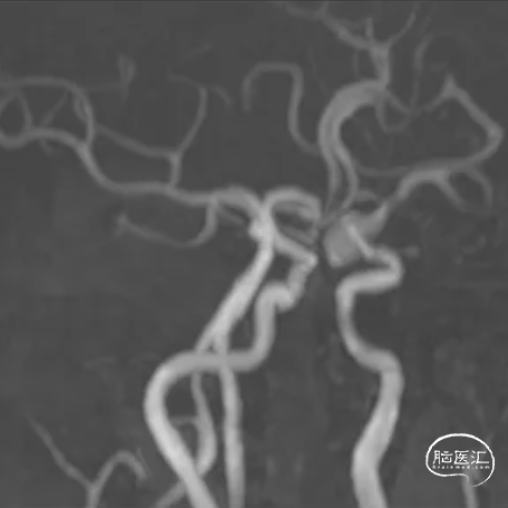

MRA及薄层T2可见左侧颈内动脉后交通段瘤样突起。

术后即刻可见支架内血流通畅,动脉瘤内可见明显造影剂滞留,远端分支显影无缺失。

术后Vaso-CT示支架贴壁良好,Xper-CT未见出血。

1年后随访影像: